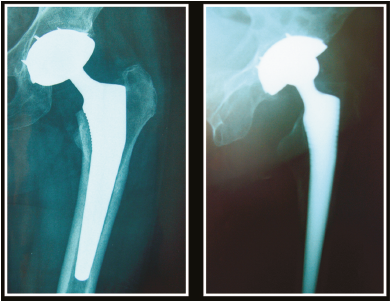

Technique : scellement d’un implant à double mobilité dans une cupule non descellée au cours des reprises de prothèse totale de hanche